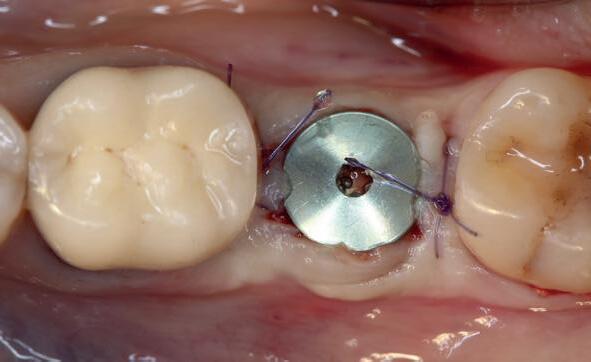

Er wordt besloten om botmateriaal te plaatsen in de extractie-alveole. Vervolgens wordt het afgesloten met een titanium versterkt d-PTFE membraan (afbeelding 2). Na vier weken wordt het membraan verwijderd.

1 2 Ridge preservation met d-PTFE membranen 35

gewonnen. De wond kan na het plaatsen van een healing abutment primair gesloten worden (Afbeelding 3a-3d).